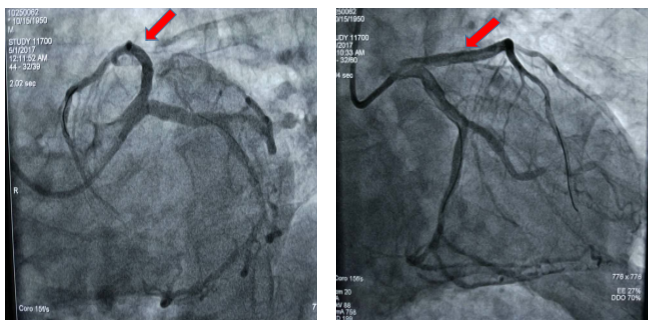

图2 患者术后冠脉造影显示冠脉血管前降支支架治疗后完全开通